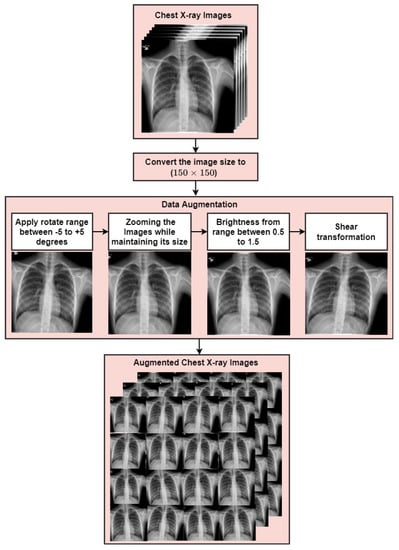

3.1. Data Augmentation

| Augmentation Strategies | Value |

|---|---|

| Rotation range | [−5, +5] |

| Zoom range | 0.95 |

| Shear range | [−5, +5] |

| Brightness range | [0.5, 1.5] |

| Tot. # of CXR after standard data augmentation | 6229 | 1498 |